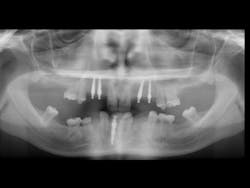

Another big reason most edentulous patients have not had implants is the constant promotion by newspapers, magazines, and TV of complex, extensive, and expensive techniques provided by some dentists and implant manufacturers. Yes, I agree that these complex plans are acceptable for some patients, but I'm convinced they're well beyond the budgets of most Americans. Thousands of edentulous patients have not been introduced to less expensive and less invasive implant treatment procedures. The majority of dentists are not using implants for edentulous patients. This treatment need is enormous, and it's only waiting for dentists to educate patients and make dentures more successful (Figures 1-3).

Figure 1 - Initial healing on two conventional diameter root form implants planned to help support and retain a mandibular complete denture.